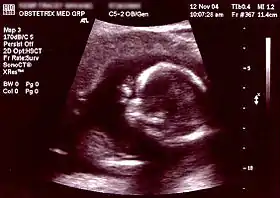

Ultrasound[8] Periodically Non-invasive/Invasive Abdominal or Transvaginal ~1 day - ~1 week Fetal development, neural tube defects, birth defects, and various other physical abnormalities (see below for specific ultrasound tests) NA

Non-invasive Ultrasound detection Commonly dating scans (sometimes known as booking scans or dating ultrasounds) from 7 weeks to confirm pregnancy dates and look for multiple pregnancies. The specialised nuchal scan at 11–13 weeks may be used to identify higher risks of Downs syndrome. Later morphology scans, also called anatomy ultrasound, from 18 weeks may check for any abnormal development. Additional ultrasounds may be performed if there are any other problems with the pregnancy, or if the pregnancy is post-due. First or second trimester